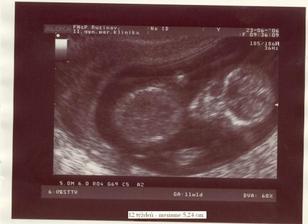

...žili dvaja šťastní ľudia, ktorým ale postupom času začalo niečo chýbať. Keď zistili čo, začalo sa krásne obdobie. Vyvrcholením tohto obdobia sa stal tretí človiečik 🙂, zatiaľ žijúci vo svojom vnútornom bezpečnom svete. Svetlo sveta by mal uzrieť začiatkom budúceho roka...